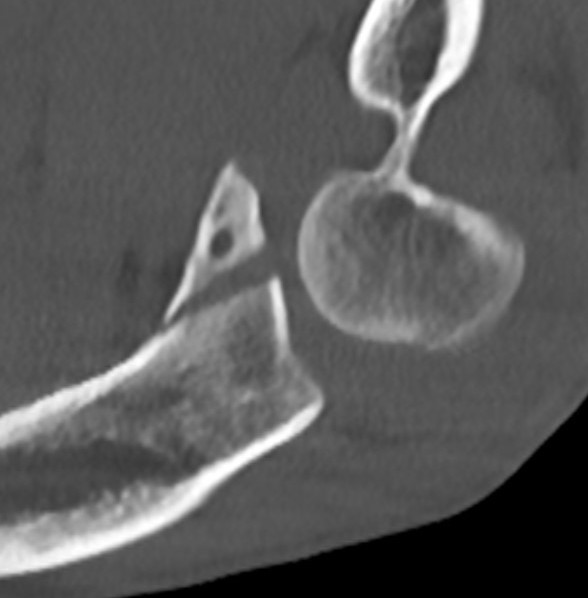

Universal posterior approach with radial head replacement and medial approach with medial buttress plate

Medial approach and buttress plate for basilar fracture with olecranon fracture